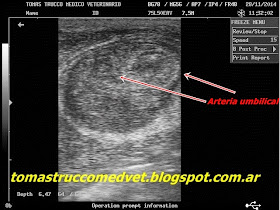

Ecografia Umbilical en terneros

| Onfalitis |